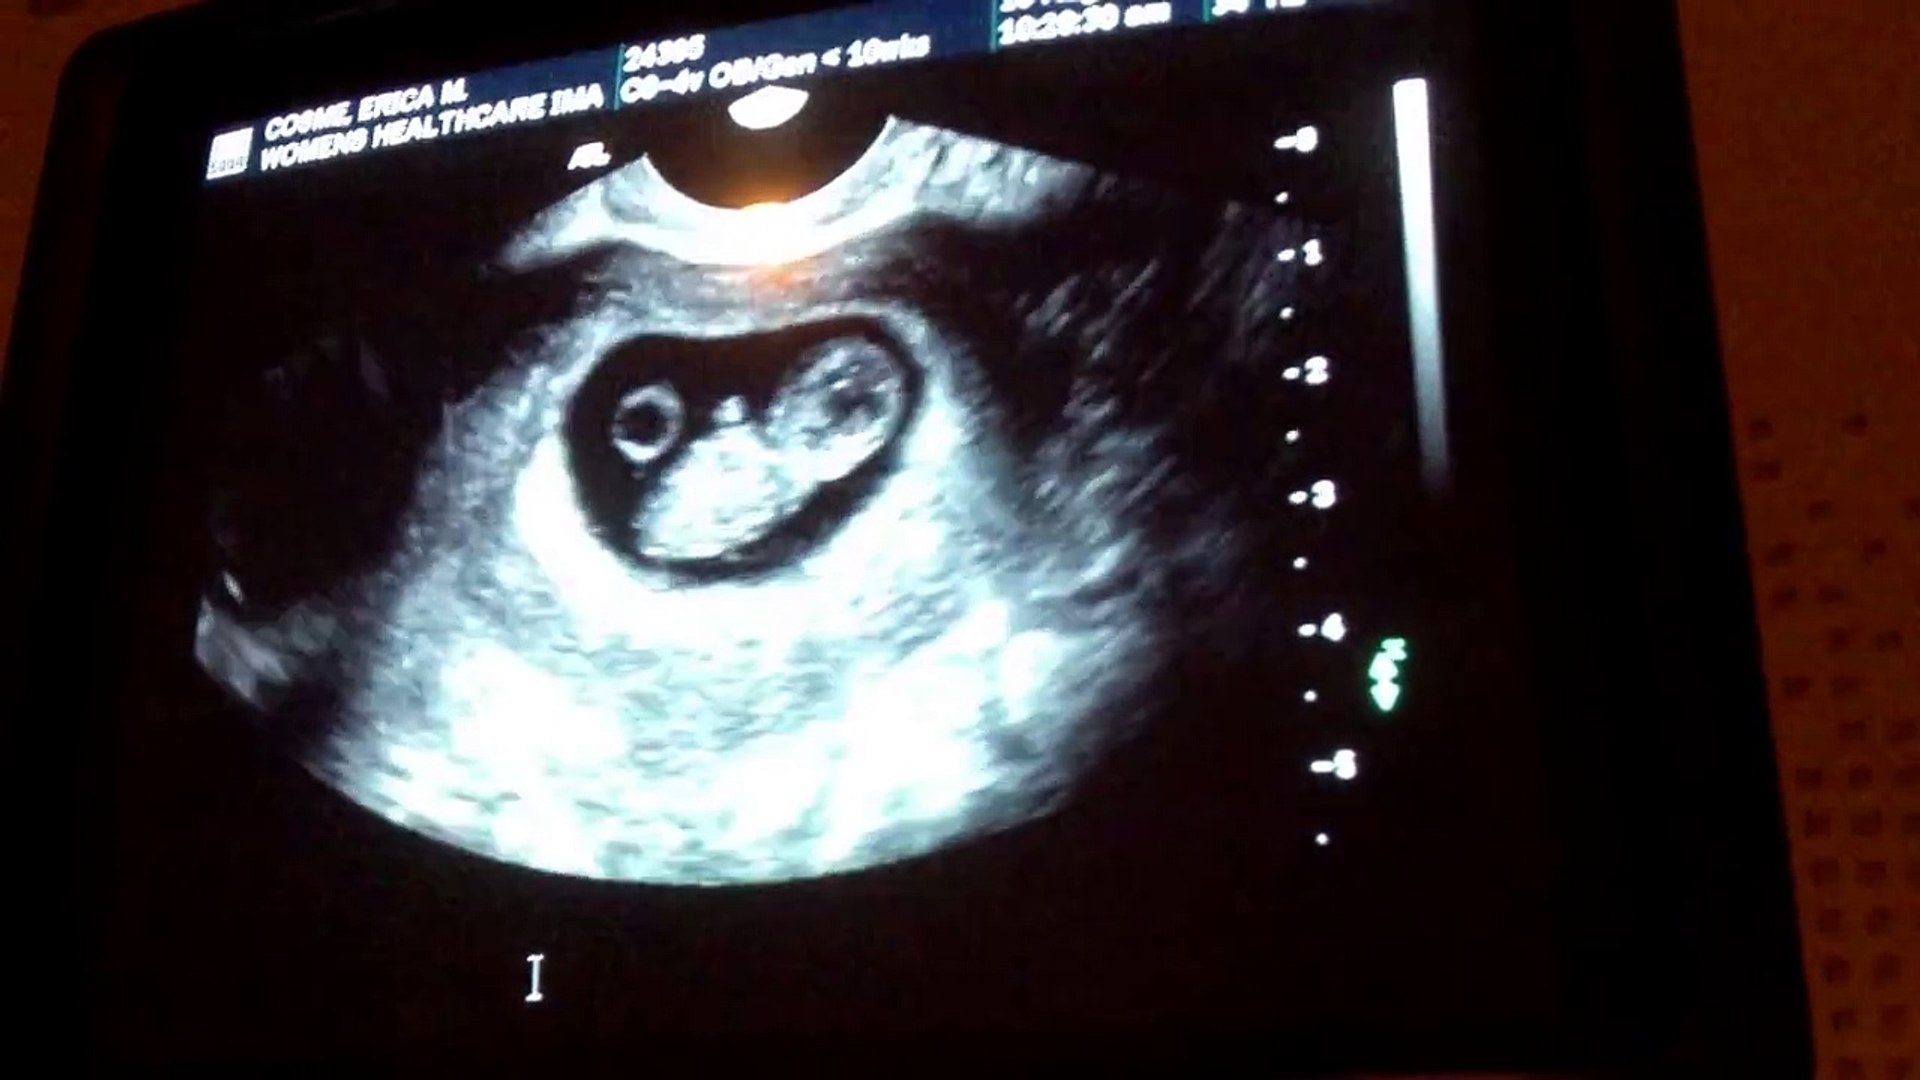

The embryo is starting to look more like a fetus, and your little one's heart and circulatory system are developing The Parriott Family 5 Weeks 6 Days Ultrasound Joined mar 26, 12 messages 37 likes received 0 i'm 5 weeks 1 day and since i got my bfp on 5th april i've been feelin sick, really hungry, tired, needin a wee more often and sore boobs then yesterday i woke up and felt fine, i felt a bit empty like not pregnant if u know what i mean and this mornings the sameYou are 5 Weeks and 6 Days Pregnant You are 6 Weeks Exactly Pregnant Your baby today The center of this image shows the baby's developing heart (darker gray), a very primitive structure at this stage The baby's head is to the right of the image The embryo is almost completely transparent There won't be any visible signs of pregnancy on the outside for some time, but

You Are 5 Weeks And 6 Days Pregnant Familyeducation